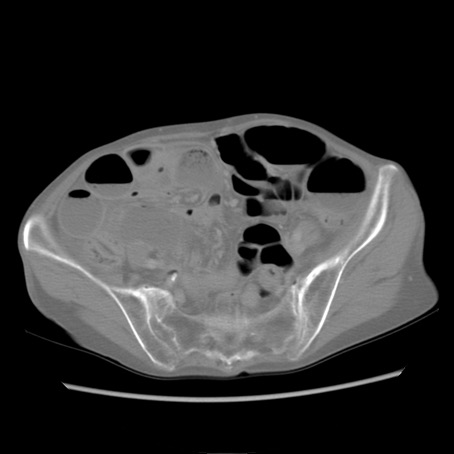

冠状断像

【症例】80歳代女性

【主訴】胸のつかえ感

【現病歴】約9時間前に食後から胸のつかえた感じあり、嘔吐あり、来院。

【既往歴】胃癌(全摘)、胆摘、虫垂炎

【身体所見】心窩部に圧痛あり、反跳痛なし。

【データ】WBC 5700、CRP 0.05